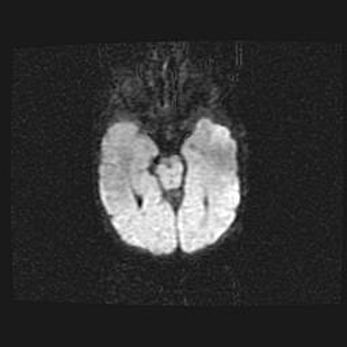

Церебральная ишемия II.

Возраст: 5 дней

Вес: 3400 г

Пол: женский

Окружность головы: 35 см

Срок гестации: 39 недель

Церебральная ишемия – это заболевание, характеризующееся недостаточностью (гипоксией) либо полным прекращением (аноксией) снабжения мозга кислородом по причине закупорки одного или нескольких сосудов. Это приводит к  что метаболическим расстройствам различной степени тяжести в тканях головного мозга, развитию коагуляционных некрозов и гибели нейронов.